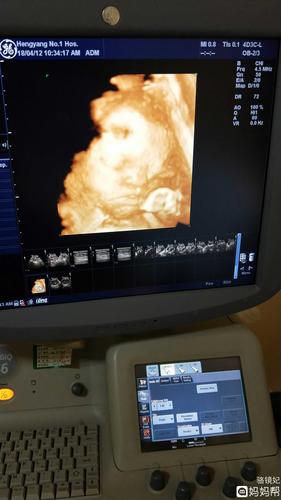

四维一次性过了!小小的你,和爸爸长这么像!

准爸爸看四维照吐槽宝宝脸大准妈妈临产前做彩超想看孩子长啥样 爸爸

这是四维的照片,和爸爸简直太像了,快看看出生后像谁呀?